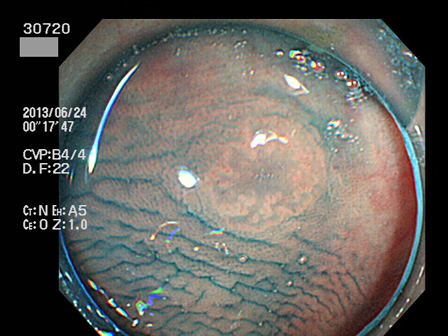

上記100名より抽出した平坦・陥凹型腺腫(=癌化の危険が高いが見落としやすい病変)の内視鏡写真